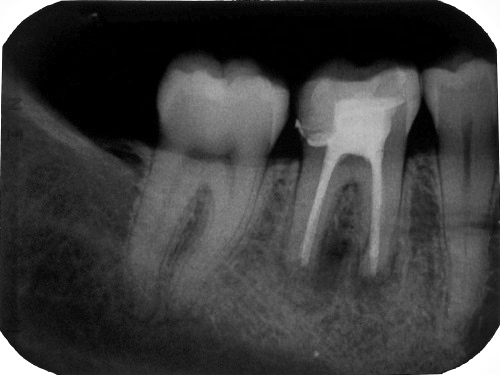

Unmittelbar nach WF nach Desinfektion nach dem Timbuktu-Protokoll im Januar 2008 bei klinischer Beschwerdefreiheit (Klick!)

Unmittelbar nach WF nach Desinfektion nach dem Timbuktu-Protokoll im März 2009 bei klinischer Beschwerdefreiheit (Klick!)